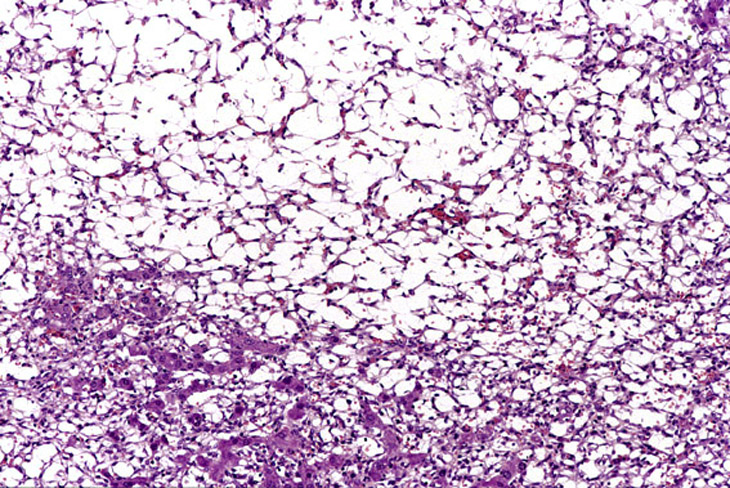

An Ito cell tumor that has replaced much of the normal hepatic parenchyma without distorting the normal contour of the liver; higher magnification shows fat-filled and stellate cells in the hepatic sinusoids.